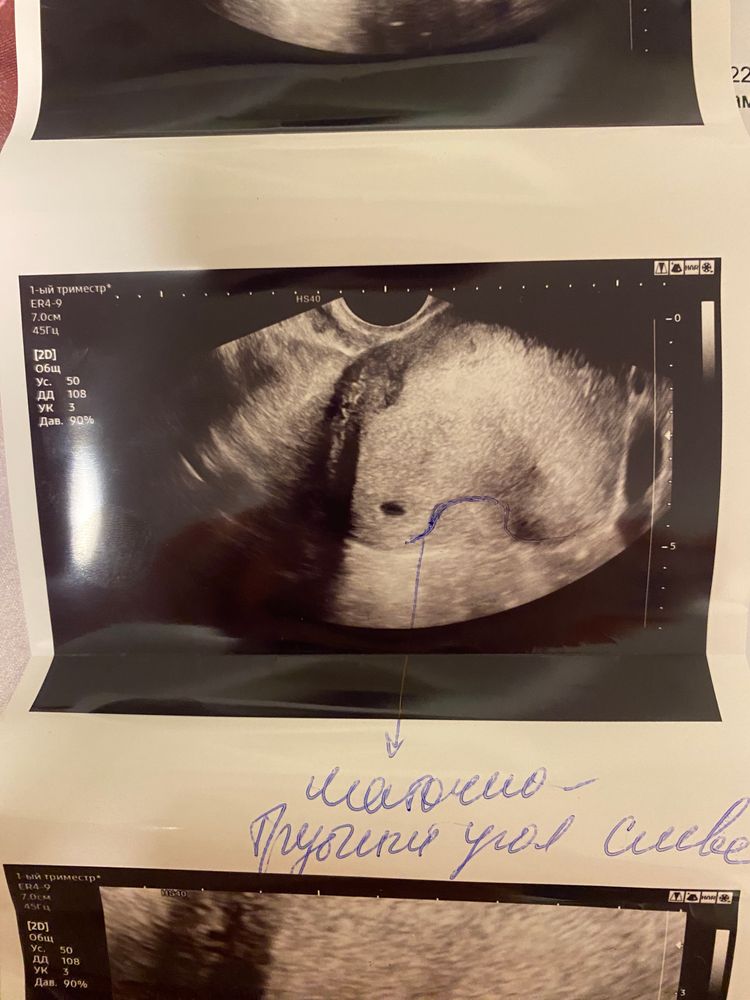

Мари в Благополучная беременность год По узи сказали ,что беременность в маточно трубном углу Анализы, скрининги Подскажите ,переместиться ли яйцо,срок беременность 4 недели и 5 дней Посмотрите еще 20 записей на эту тему Отменить Ответить Екатерина Обязательно переделать узи. Если все подтвердится, к сожалению, придется прерывать. Плодное яйцо уже не переместится 05.12.2024 Ответить Анютка В любом случае переделать узи, а вообще наверное прогнозы не очень хорошие, если реально в углу. 05.12.2024 Ответить Maria Нет, яйцо будет расти на одном месте. Вам врач что сказал ? 05.12.2024 Ответить Как сдать посев мочи Канефрон Чаты Беременных Выберите чат: Январята-2026 Февралята-2026 Мартята-2026 Апрелята-2026 Майчата-2026 Июнята-2026 Июлята-2026 Августята-2026